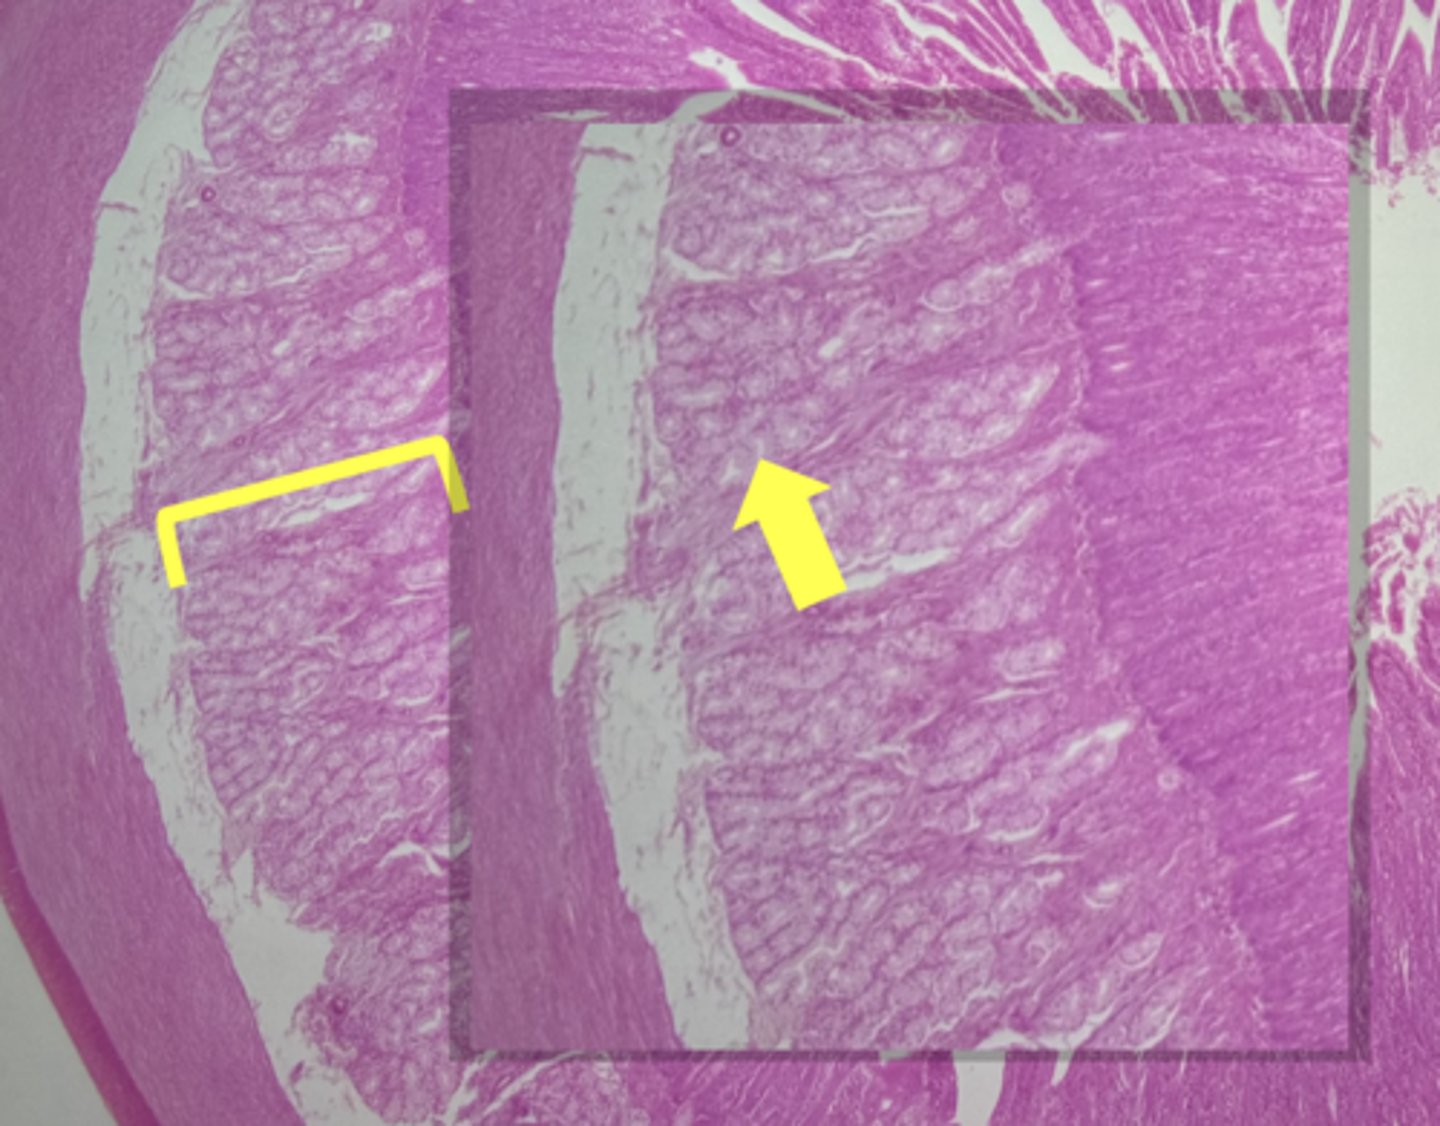

Esophagus

name the tissue

Mucosa

(esophagus)

Submucosa

muscularis externa

stratified squamous epithilium (KEY CHARACTERISTIC)

lamina propria

muscularis mucosae

circular layer

longitudinal layer

A- Esophagus

B- Stomach

Name the Tissue A & B